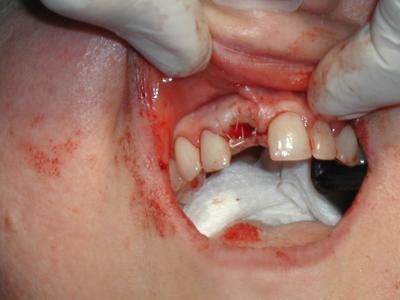

Вероятность появления неприятного запаха и привкуса во рту после удаления зуба значительно снижается при последующих правильных действиях врача. Специалист внимательно просматривает корни, чтобы удостовериться в их целостности. После этого осматривается сама лунка: малой ложечкой врач исследует рану, в случае обнаружения осколков зуба или частичек альвеолы – удаляет их.

Если после удаления зуба, несмотря на качественно выполненную врачом работу, все же пахнет изо рта, необходим повторный визит в стоматологический кабинет. Стоматолог промоет лунку перекисью водорода либо раствором марганца, предварительно введя местную анестезию (например, Новокаин). Возможно, будет назначен физиотерапевтический курс лечения.

В домашних условиях необходимо ополаскивать ротовую полость теплым раствором марганца 3-4 раза в день. В случае необходимости, стоматолог пропишет прием обезболивающих препаратов, антисептиков и антибиотиков.

Выполняя все рекомендации врача неприятный запах, возникший после удаления зуба, исчезнет через 10-12 дней.

Сначала пациенту колют анестезию, удаляют налёт. Потом рана обрабатывается антисептиком. Во вскрытую лунку закладывается сильнодействующее лекарство. На рану накладываются швы. Человек ходит с лекарством, пока десна не перестанет болеть и зловоние не исчезнет. Когда рана затянется, допустимо устанавливать протез на место удаленного зуба.

Вероятность появления неприятного запаха и привкуса во рту после удаления зуба значительно снижается при последующих правильных действиях врача. Специалист внимательно просматривает корни, чтобы удостовериться в их целостности. После этого осматривается сама лунка: малой ложечкой врач исследует рану, в случае обнаружения

осколков зуба или частичек альвеолы – удаляет их. Производится очищение стенок лунки и, по необходимости, зашивание десны. На рану накладывается тампон, который нужно прикусить и подержать минут 15 – 20. Дольше удерживать тампон не следует, потому что он мешает оформиться сгустку крови.

Если после удаления зуба, несмотря на качественно выполненную врачом работу, все же пахнет изо рта, необходим повторный визит в стоматологический кабинет. Стоматолог промоет лунку перекисью водорода либо раствором марганца, предварительно введя местную анестезию (например, с помощью новокаина). Возможно, будет назначен физиотерапевтический курс лечения.